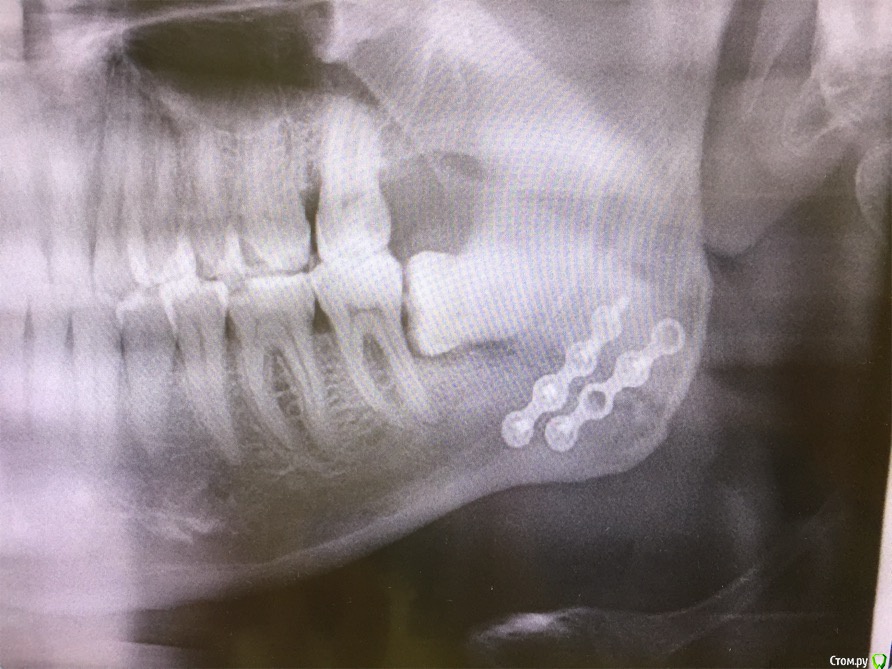

cinovka Опубликовано 10 сентября, 2015 Поделиться Опубликовано 10 сентября, 2015 Здравствуйте. Помогите советом. 15 августа получил перелом нижней челюсти с левой стороны в районе 7-8го зуба.25 числа наложили титановую пластину на место перелома и зашинировали. 3 сентября сняли шины. Разрез делали в ротовой полости и снаружи, для закрутки шурупов.Наружную рану опять вскрыли 1го сентября, т к началось нагноение. Гной выходит постоянно уже 9й день. все болит. зуб мудрости лежит в десне и очень сильно болит.Прошла неделя после снятия шин, а рот также не открылся. максимально открывается на 1-1,2 см.Я нахожусь за границей и врач мой толком ничего не обьясняет.Ответьте пожалуйста на следующие вопросы : 1) Кода пройдет нагноение? И почему оно произошло? (антибиотики, повязки и полоскания постоянные). 2) Когда откроется челюсть? 3) Когда можно будет удалить лежачий зуб мудрости? Снимки номер 1,2,3,4 сделаны до операции 17 августа.Снимки номер 5,6 сделаны сегодня 10 сентября. Заранее спасибо за ответы. Жду с нетерпением. Алексей. Ссылка на комментарий

kriokov Опубликовано 10 сентября, 2015 Поделиться Опубликовано 10 сентября, 2015 Вопрос с костным фрагментом слева,возможно он секвестрируется. чего пациента пугать. Там только два фрагмента, большой и малый, две "линии перелома"- это просто обычная картинка , редко когда ломают челюсть как по линейке, равнозначно с вестибулярной и язычной поверхности. Короче-- не секвестр 3 Ссылка на комментарий

колесников Опубликовано 10 сентября, 2015 Поделиться Опубликовано 10 сентября, 2015 Короче-- не секвестрна последнем снимке не всё так очевидно,+ гноетечение из этой области, + сроки... короче зуб не дам . 1 1 Ссылка на комментарий

ПалСаныч Опубликовано 10 сентября, 2015 Поделиться Опубликовано 10 сентября, 2015 С колесниковым не согласен категорически. Полностью поддерживаю криокова. Это не секвестр, это наложение двух линий перелома с внутренней и наружной стороны. Если б ко мне попал пациент с такой проблемой, то я предложил бы ему такую тактику: 1 пластины снять нафиг, потому чо они там не работают, ибо наложены стнарушением правил остеосинтеза, а так же потому что в ране гной; 2 во время снятия пластин через разрез задренировать рану и провести антибактериальную терапию; 3 наложить опять шины если есть подвижность отломков после снятия пластин. 4 зуб убрать вместе с пластинами. Все написанное ИМХО. 6 1 Ссылка на комментарий

cinovka Опубликовано 11 сентября, 2015 Автор Поделиться Опубликовано 11 сентября, 2015 У Вас остеомиелит челюсти.Если зуб не удалить,перелом не зарастёт никогда.Надо решать этот вопрос незамедлительно.Вы в каком городе находитесь сейчас?Есть ли возможность вернуться в Москву?Вы уверены: что у меня остеомиелит? Врач сказал, что его нет. Предоставление снимки сделаны круговым рентгеном, а не просто с левой стороны. Врач пояснил, что поэтому кажется что там две трещины. Возможно Вы в курсе, извините. Ссылка на комментарий

kriokov Опубликовано 11 сентября, 2015 Поделиться Опубликовано 11 сентября, 2015 1. По Вашим жалобам и клинике тянет на остеомиелит, точно только очно можно2. Вам сделали оптг, аппарат ходил кругом как Вы выразились. При таком снимке, да и при выполнении снимков другими методами линий перелома кажется что две, на самом деле плоскость перелома одна (ПалСаныч выше описал)3.учитывая, что гноетечение и со стороны полости рта в обл 8 и снаружи из послеоперационной раны и отек лица держится выраженный я бы члх еще раз потревожил, не решите на месте, надо возвращаться. Имхо Ссылка на комментарий